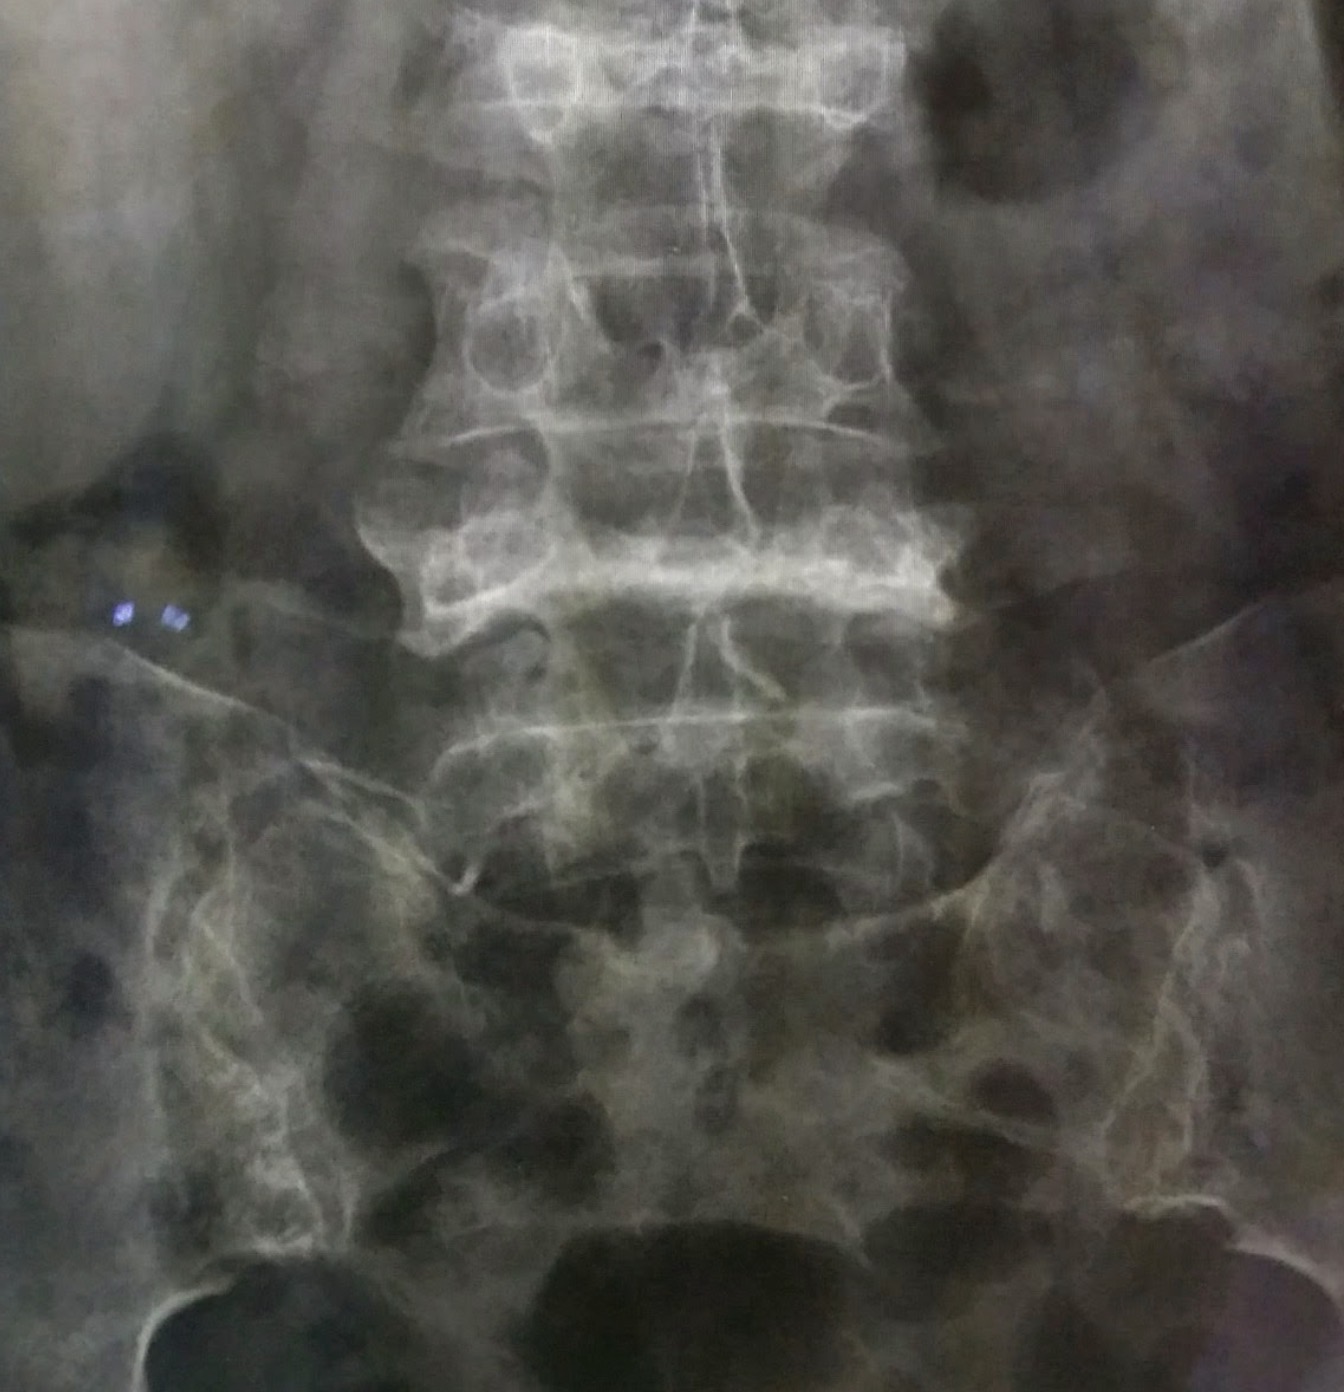

เอกซเรย์ธรรมดาของเชิงกรานมัก “ไม่เห็นรอยร้าว” ในระยะต้น ทำให้โรคนี้ถูกมองข้ามได้ง่าย การวินิจฉัยที่แม่นยำ จึงต้องอาศัยการตรวจขั้นสูงมากขึ้น

- MRI เชิงกราน เป็นการตรวจที่สำคัญที่สุด เห็นทั้งรอยร้าวและการบวมในไขกระดูก (bone marrow edema) บอกตำแหน่งและจำนวนรอยร้าวได้ชัด เช่น sacrum เป็นรูปตัว H หรือร้าวที่กระดูกหัวหน่าวสองข้าง

- CT scan ช่วยดูรายละเอียดกระดูก ถ้าต้องแยกจากมะเร็งกระจายหรือเนื้องอกอื่น